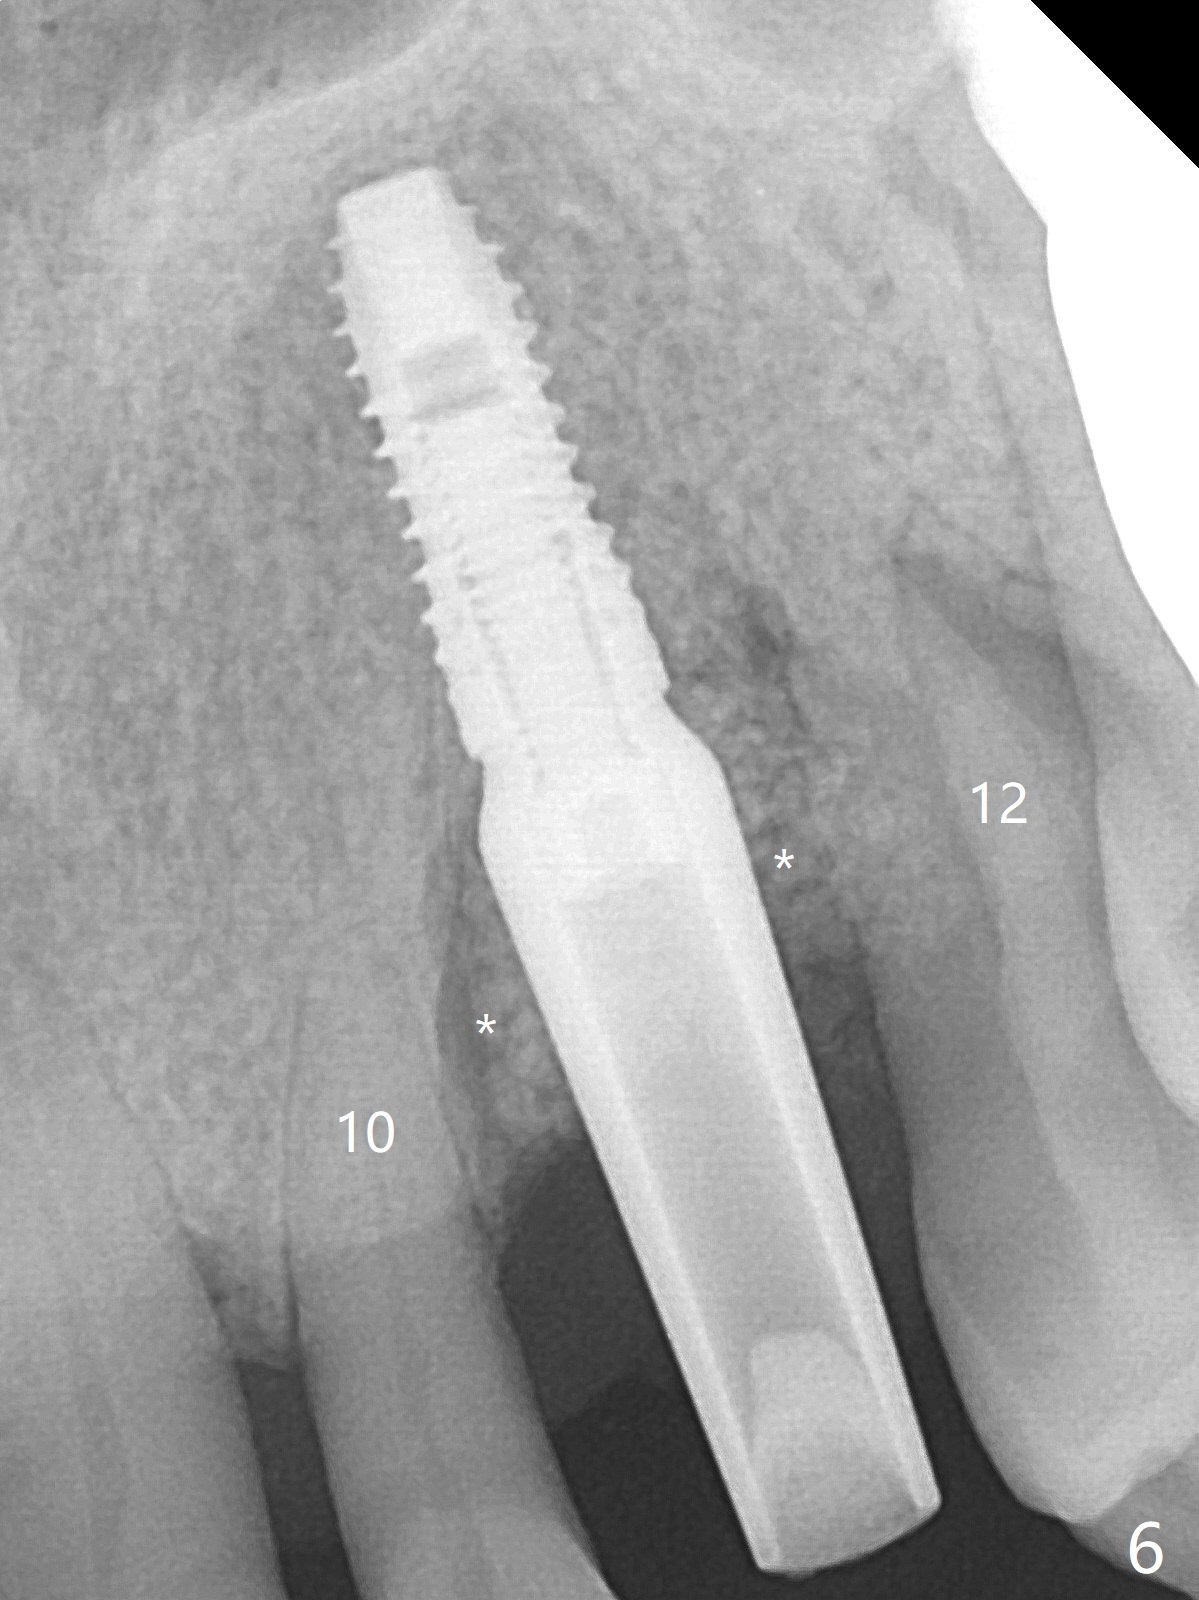

A 62-year-old man with generalized chronic periodontitis returns with chief complaint of loose tooth at #11 (Fig.1). Although a buccal fistula (Fig.1 <) is closer to #12 than to #11, percussion is more severe at #11 than 12. The buccal plate of #11 is missing, but it is possible to place a narrow immediate implant because of the wide alveolus (Fig.2). Since the gingiva is ~ 10 mm long, a mill abutment is to be used (Fig.3,5). In fact the fistula communicates with #11 extraction socket. After debridement, osteotomy is initiated (Fig.4) for a 3.8x10 mm implant ~ 35 Ncm, followed by seating a 4.5x2 mm mill abutment (Fig.5). Abundant sticky bone is placed in the remaining socket (for buccal plate reconstruction) and against the root surface of the neighboring teeth (Fig. 6 * (#10,12)). Finally 2 pieces of PRF membranes are utilized to facilitate repair of the buccal soft tissue defect (Fig.7 *). The root prominence of the canine seems to be maintained by the bone graft (Fig.8 C). Acrylic dressing holding the PRF membranes in place remains in situ with the healthy gingiva buccal (Fig.9) and palatal (Fig.10) 11 days postop. Note the acrylic locking into the undercuts of the neighboring teeth (*). 经过一段摸索发现离心每分钟1500转5分钟后,抽取上清液,接着再离心10分钟剩余上清液就形成血小板块,压制后便是血小板膜,后者似乎有助于软组织愈合,而上清液用来制备骨块,帮助硬组织生长。利用这个原则讨论以下病例治疗。The gingival margin gains ~ 5 mm 6 weeks postop when the acrylic dressing is removed (Fig.11,12 (<: previous one), as compared to Fig.7,8). 治疗结束时尖牙牙龈缘高于第一双尖牙(图七,八),六个星期后,尖牙牙龈缘却低于双尖牙(图十一,十二(箭头:原始牙龈缘))。术后2.5,4.5月基台周围牙龈似乎能与钛合金附着,防止细菌进入深部植体(图十三,十四)。临时牙冠脱落多次,可能与mill abutment太光滑有关,所以颊侧,舌侧磨成平面(图十四)。取模时好像不必取出基台清洗(仿佛没有炎症),原位用树脂延长基台。术后5个月CT显示颊侧骨板再生(图十六-十八)。取模时并没有用树脂加长基台;粘固时,牙冠颜色理想,但是照片中并不是如此(图十九,二十),颊侧骨板没有塌陷。术后11个月基台颊侧骨板没有萎缩(图二十一:B);3d图像:骨壁完全形成(图十六对比:部分形成)。密度也增高(图二十二:B),与术后五个月比较(图十七)。术后十一个月,粘固后五个月角化龈存在(图二十三),牙冠颈部有金属颜色透出,是因为二段式基台太粗了(最细4.5毫米),可以请实验室在牙冠内部涂opaque material而减轻。